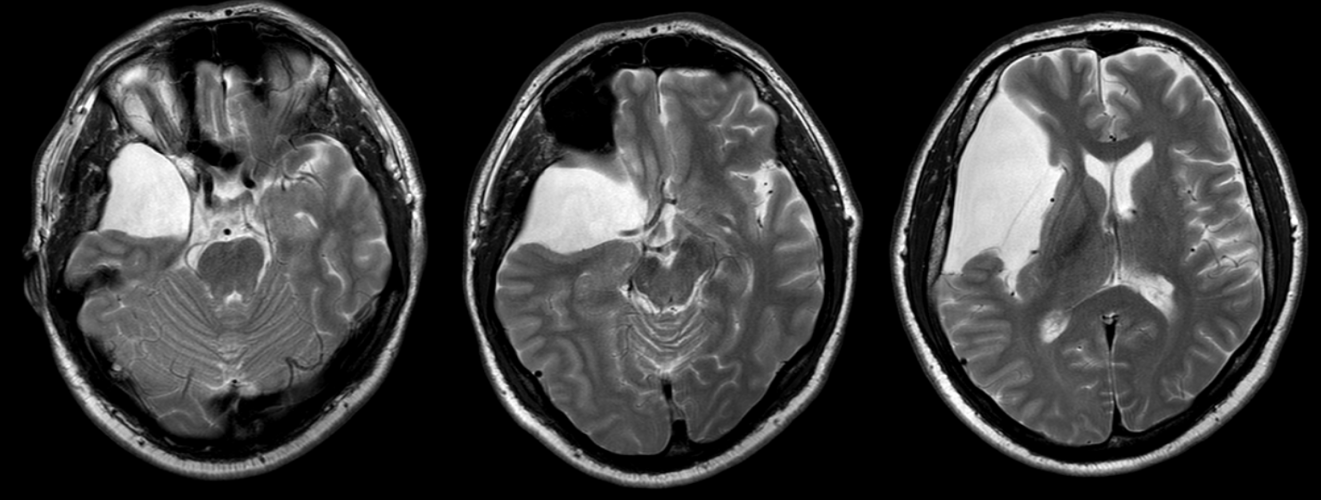

Imagistica este esențială pentru identificarea chistelor arahnoidiene:

- RMN (rezonanță magnetică nucleară): metoda preferată, evidențiază conținutul de LCR și raporturile cu structurile cerebrale.

Chistul arahnoidian apare ca o leziune hipointensă pe imaginile T1 și hiperintensă pe imaginile T2, cu semnal identic cu cel al lichidului cefalorahidian.